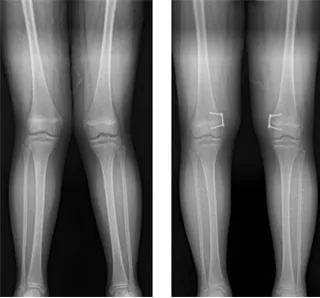

신생아는 대부분 O자형 다리로 태어나 2세 전후 곧게 펴지며, 3~4세에 일시적으로 X자형으로 변했다가 6~7세에 정상 정렬로 성장한다. 일부 소아에서는 구루병이나 유아 경골 내반증 등 병적 원인으로 휜 다리가 지속되거나 심해질 수 있다.

만 3세 이하는 보조기 사용을 시도할 수 있으나 효과가 증명되지 않았고, 사춘기 이후에는 반성장판 유합술이나 교정 절골술 같은 수술적 치료가 필요하다. 성장판이 닫히기 전인 남아 12~14세, 여아 10~12세 사이의 조기 치료가 가장 효과적이다.